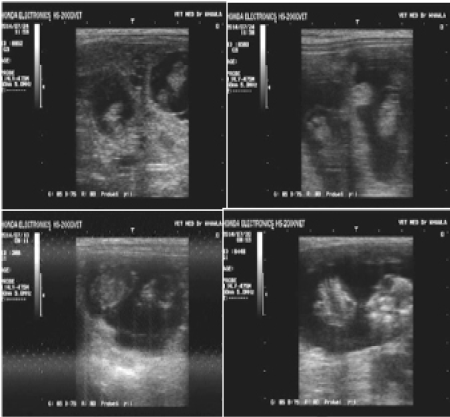

Pregnancy diagnosis of goats by ultrasonography : a. twin in 30 days, b. twin in 35 days, c. single in 50 days, and d. single in 55 days